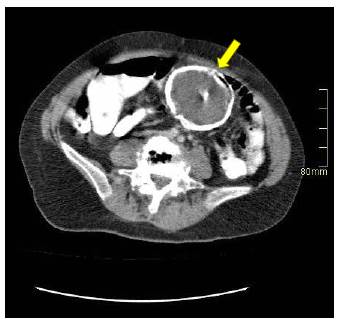

Por sospecha de lesión de origen ginecológico es valorada por los servicios de ginecología y gineco-oncología, quienes ampliaron el estudio de la masa con marcadores tumorales (antígeno carcinoembrionario 0,79 ng/ml, alfa fetoproteína 1,64 ng/ml y CA 125 12,3 U/ml) los cuales se encontraron dentro de límites normales. En adición se realizó tomografía computarizada (TC) de abdomen (figura 1) que mostró calcificación en el fondo uterino, probablemente por miomatosis calcificada y una masa de densidad negativa (grasa) encapsulada con calcificación anular alrededor de la misma, localizada en el mesenterio con medidas de 70 x 66 x 73 mm, por lo cual se consideró posible la presencia de necrosis grasa encapsulada antigua versus una neoplasia primaria del mesenterio, como tumor desmoide.